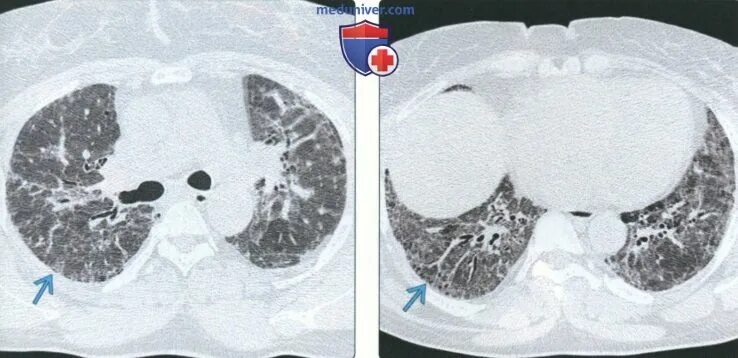

Гипостатические изменения кт